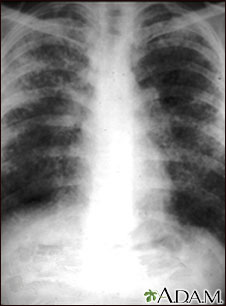

Sarcoid causes damage to the lung tissue that heals by scarring. The film shows a diffuse milky and granular appearance in the normally dark lung areas. This individual has marked decrease in lung function.